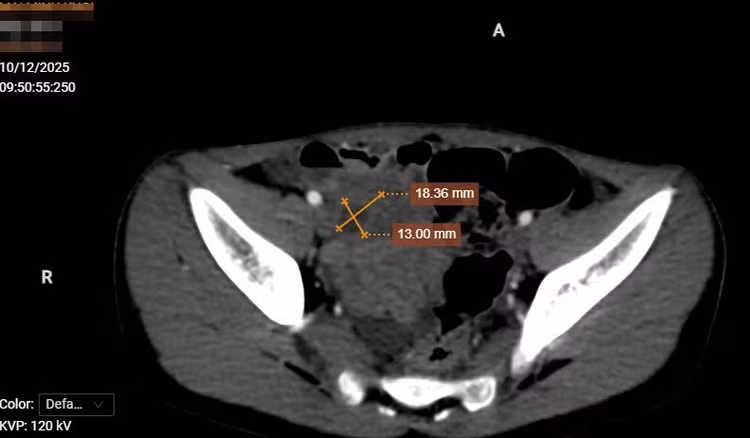

Hình ảnh vỡ nang ruột đôi trên phim chụp - Ảnh BVCC

Sau khi bệnh nhân được siêu âm và cắt lớp vi tính thấy: Hố chậu phải có cấu trúc dạng dịch, thành của cấu trúc này có các lớp giống với các lớp của thành ống tiêu hóa, ngấm thuốc mạnh sau tiêm. Dịch bên trong cấu trúc này không đồng nhất. Thành của cấu trúc này có vị trí mất liên tục, thâm nhiễm xung quanh.

Ngay lúc này, bệnh nhân được hội chẩn liên chuyên khoa bởi các bác sĩ Chẩn đoán hình ảnh, Ngoại tổng hợp, Gây mê hồi sức. Bệnh nhân được chẩn đoán viêm phúc mạc khu trú hố chậu phải nghĩ đến nguyên nhân do nang ruột đôi vỡ. Các bác sĩ đã thống nhất thực hiện phẫu thuật mổ cấp cứu cho bệnh nhân.